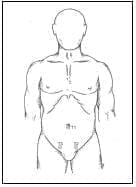

FIGURA 1. Distribución de los trocares con vía de acceso suprapúbico.

La cirugía laparoscópica siempre fue practicada a cabo por dos cirujanos expertos y la descripción de la técnica operatoria fue como sigue: el procedimiento se llevó a cabo con el paciente en posición supina con los brazos pegados a ambos lados del cuerpo. Para tener una buena visión del campo quirúrgico y evitar yatrogenias durante la punción de los trocares, la vejiga se vació espontáneamente en el preoperatorio inmediato con el fin de evitar el uso de una sonda vesical. El monitor de video se colocó a la derecha del paciente y el equipo de cirujanos a la izquierda del mismo. En esta posición el cirujano principal operó con ambas manos y el cirujano ayudante manejó el laparoscopio. El neumoperitoneo se obtuvo usando la técnica cerrada a nivel umbilical y se insufló el abdomen con dióxido de carbono hasta alcanzar una presión de 12 mm Hg. Para la colocación de los puertos de entrada, se usó la técnica de abordaje suprapúbico (figura 1), que consiste en la introducción de un primer trocar de trabajo de 10 mm (T1) a nivel umbilical, por donde ingresa inicialmente un laparoscopio de 30º (figura 2); luego, bajo visión directa se insertaron otros dos trocares a nivel suprapúbico: un trocar izquierdo (T2) de 10 mm y un trocar derecho (T3) de 5 ó 10 mm.